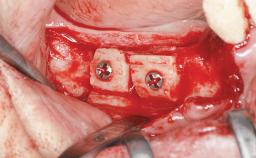

Replacement of Multiple Teeth in a Partially Dentate Posterior Mandible with a Fixed Dental Prosthesis Using a Flapless Approach

Bone Augmentation No

Guided Surgery Yes